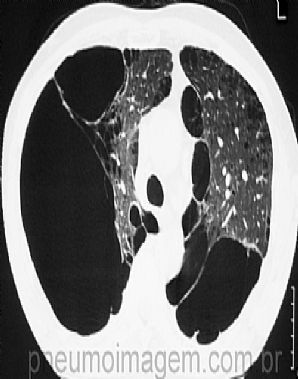

LANÇADA A VERSÃO 2014 DO DOCUMENTOFoi lançada versão 2014 de atualização do documento GOLD (Global Initiative for Chronic Obstructive Lung Disease). Esse relatório é apresentado como um documento estratégico para os profissionais de saúde usarem como ferramenta para implementar programas eficazes de cuidados em DPOC.

A ferramenta de classificação da DPOC baseada no quadrante foi projetada para ser usada em qualquer ambiente clínico. Ela reúne uma avaliação funcional, uma medida do impacto dos sintomas do paciente e uma avaliação do risco de ocorrência de um evento adverso grave no futuro do doente.